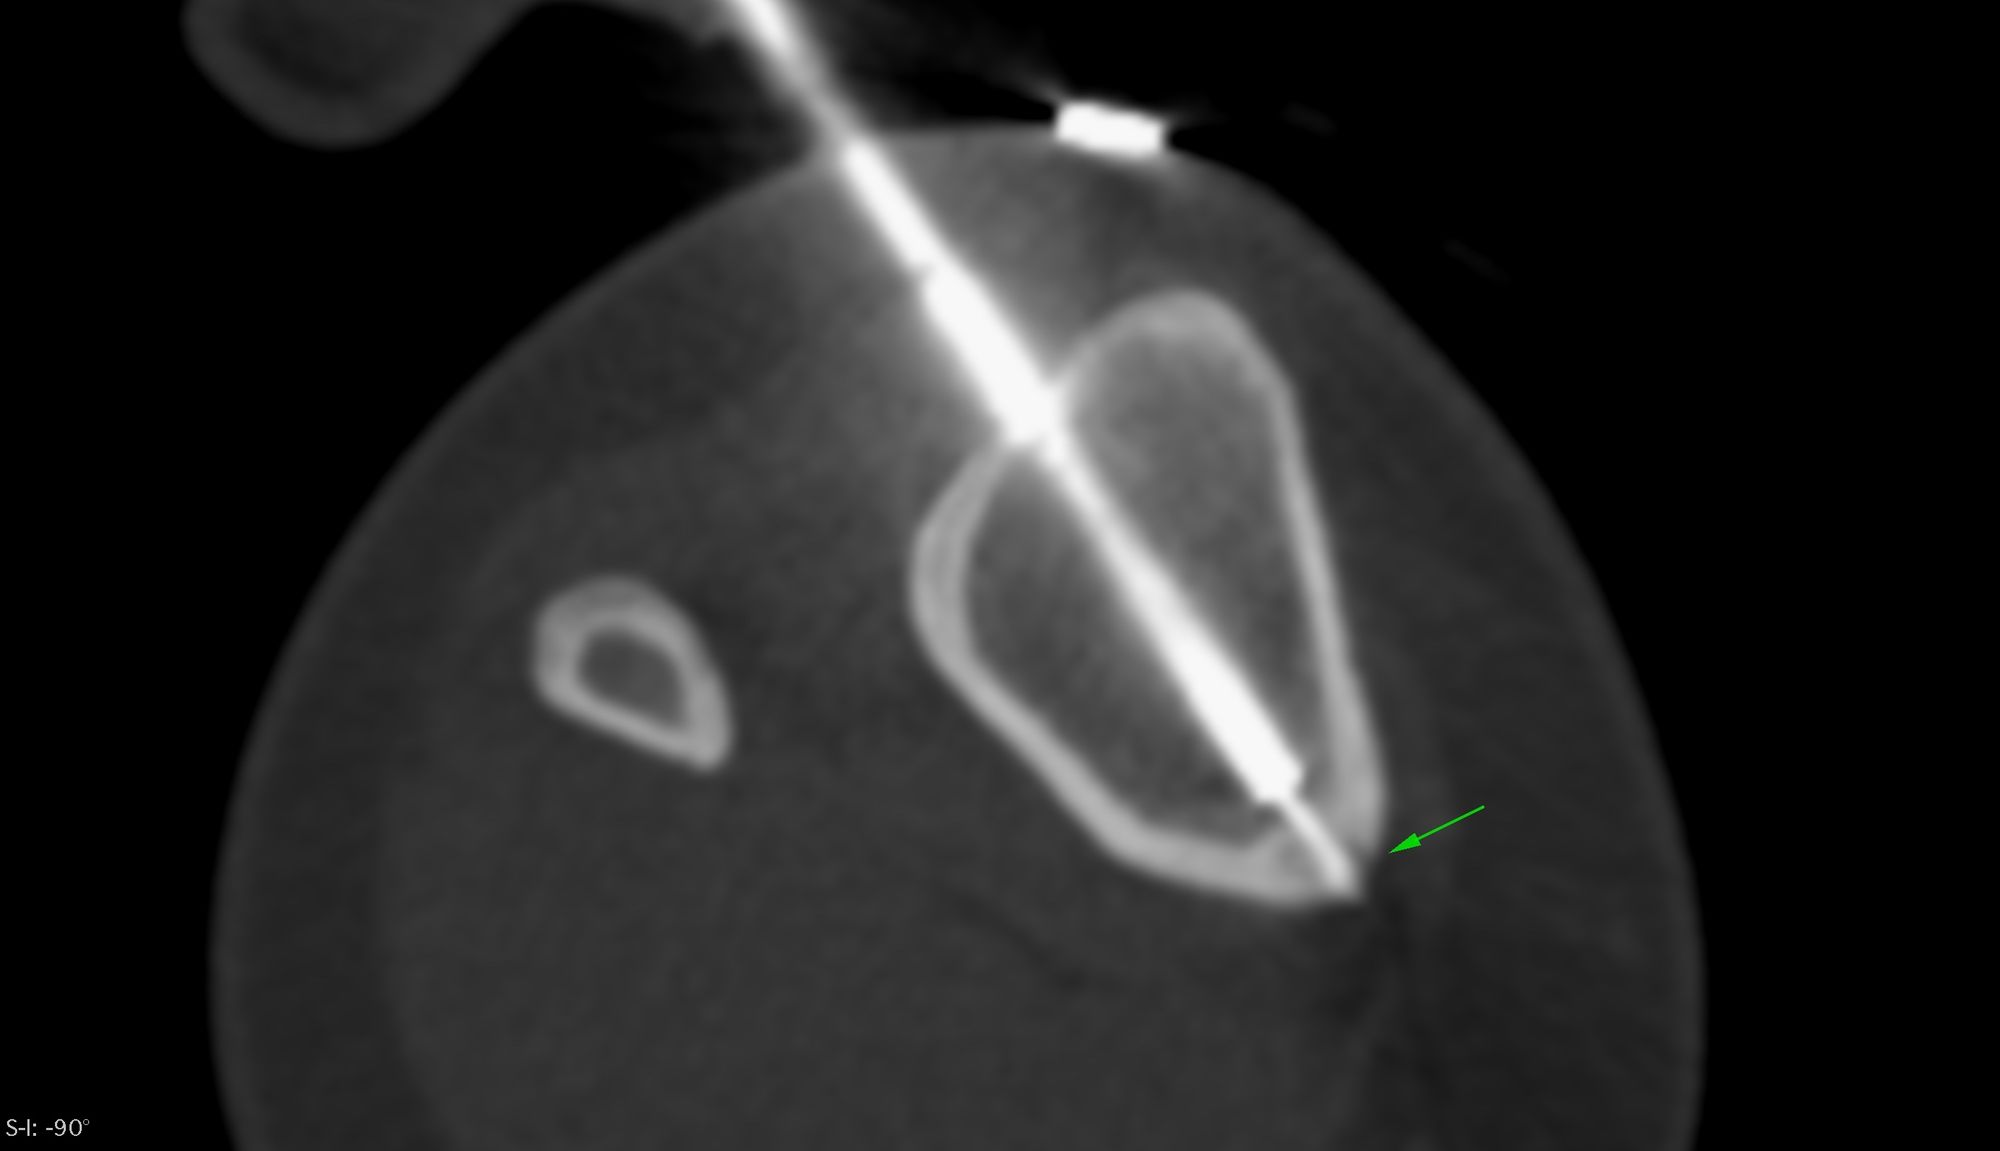

Case 7: Radiofrequency Ablation (RFA) - Tibial Osteoid Osteoma